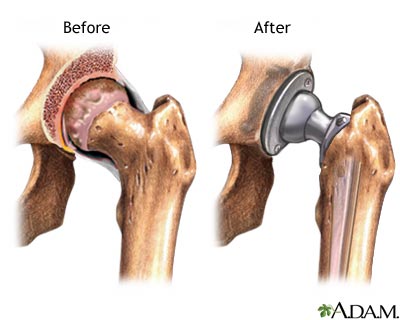

Hip joint replacement - series: Aftercare

Results with a hip prosthesis have been excellent. The operation relieves pain and stiffness symptoms, and most patients (over 80%) need no help walking. With time, loosening of the artificial joint has been observed due to the limited properties of the cement used to attach the artificial parts to the bones.

Positioning is very important after surgery to reduce stress on the new joint and displacement of the joint. The new hip will not have the same range of movement of the original joint, although you should eventually be able to return to your previous level of activity. However, you should avoid vigorous sports such tennis, skiing, or contact sports.